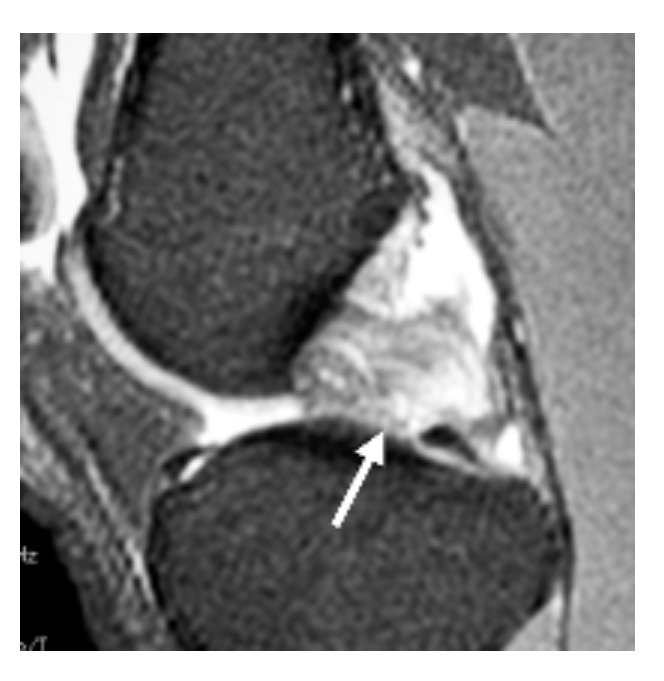

صورة #الرنين_المغناطيسي لمريض لديه #قطع_الرباط_الصليبي_الخلفي